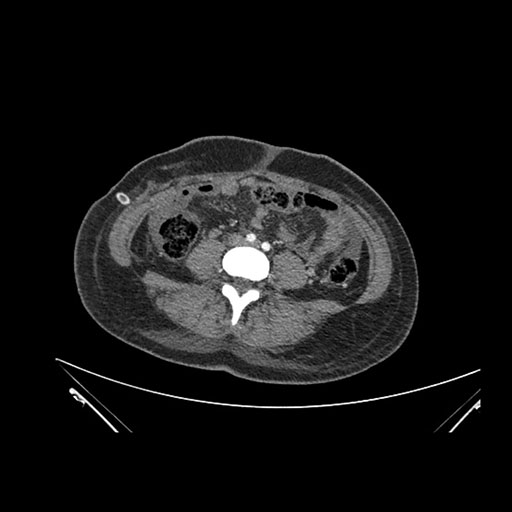

Imaging Analysis

Look through the patient's CT scan to identify any areas of concern for the necessary procedure.

Axial Venous